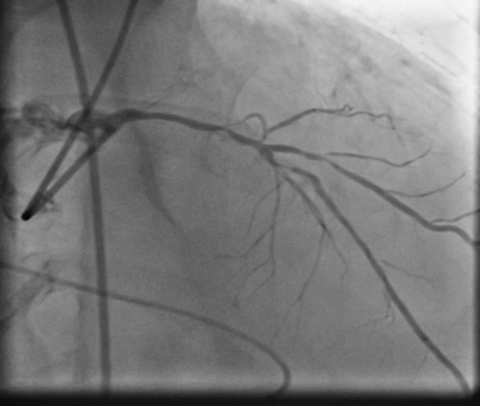

patient underwent coronary angiogram which revealed calcified triple vessel disease with near total occlusion of proximal RCA and 80% calcified stenosis in mid LAD with diseased small circumflex artery. In view of very high surgical risk he was turned down by surgical team and was advised for a high risk PCI of infarct related artery on hemodynamic support in form of IABP which was only mechanical circulatory support available apart from VA-ECMO.

PCIof right coronary artery was initiated on IABP support with amplatz left1 guided catheter and vessel was crossed with great difficulty in repeatedattempts by fielder XT followed by GAIA 2 wire over corsair microcatheter. Microcathetercould not be crossed beyond mid segment calcified CTO, so balloon dilation with0.75 mm balloon was done after which again microcatheter could not be trackedbeyond mid part. Butwe were able to exchange wire to allstar followed by rotawire byplacing microcatheter in mid segment after balloon dilation by 0.75 mm balloon. Rotablation wasdone with 1.25 mm burr at 1,60,00 rpm repeatedly from proximal to mid distalpart. Lesionstill looked unprepared as repeated postdilation with2.25*15 mm followed by 2.5*15 mm non compliant balloon at high pressures showedunexpanded balloon. Againlesion preparation was done with 2.5*15 mm wolverine cutting balloon repeatedlyat high pressures which led to adequate luminal gain and calcium cracks as seenon IVUS run. AfterIVUS run again high pressure balloon dilation was done with wolverine 2.5*15 mmballoon followed by 2.5*12 mm non compliant balloon at 28 atm toadequately prepare the lesion before stent deployment. Stentingwas done with 2.5*32 mm DES, 2.75*32 mm DES, and 3*24 mm DES from distal toproximal in overlapping fashion. Thenfinally high pressure post dilation was done with 2.75*15 mm followed by 3*15mm non compliant balloon and adequate stent expansion was achieved with TIMI 3 flow.